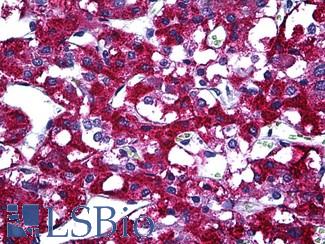

Prostate Specific Antigen (KLK3)

Anti-KLK3 / PSA antibody IHC of human prostate. Immunohistochemistry of formalin-fixed, paraffin-embedded tissue after heat-induced antigen retrieval. Antibody LS-B3470 dilution 1:200.